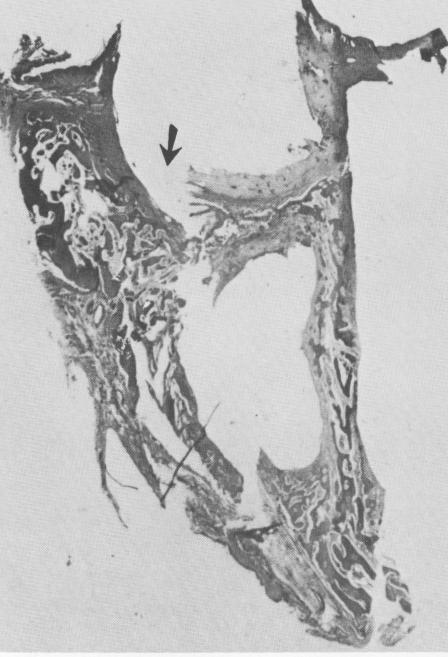

Fig. 4-77. A distinct line of osteoblasts (arrow) appears in this higher magnification of the bridge. (Courtesy M. Hodosh.)

1 Osteoblasts in line of endosseous crystalline implant bridge